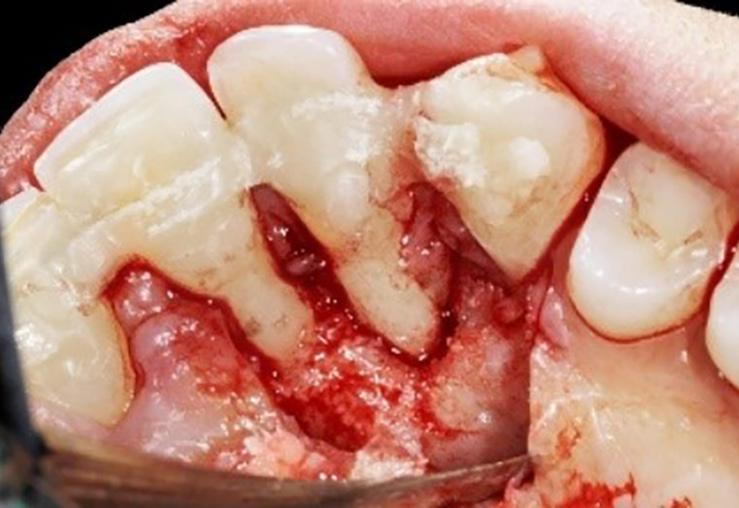

Los dientes anteriores (n.º 13 23) se feru lizaron con una férula periodontal Rib bond, y la oclusión se ajustó a un contac to ligero. Se elevó un colgajo de espesor total, y el defecto se descontaminó con una combinación de láser de CO2 de 9,3 micras y EDTA al 24 %. Después de la descontaminación confirmamos un de fecto de una pared con una bolsa perio dontal intraósea de 7 mm. Injertamos el defecto con Geistlich Bio‑Oss® Collagen, que tiene una excelente capacidad para actuar como andamiaje y resulta muy útil en esta indicación.1 Después cubrimos el injerto óseo con L PRF™ para una mejor respuesta angiogénica de los tejidos.

La paciente fue sometida a un seguimien to de 12 meses, donde se puso especial atención a la regularidad de las visitas y a la higiene oral. Al año del seguimiento y en la reentrada para mejorar el perfil del teji do blando, confirmamos que el defecto se había rellenado por completo con hueso nuevo con una adaptación estrecha a los

| A Antes del tratamiento ortodóncico. | B CBCT periapical antes del tratamiento periodontal. | C Dientes (13 y 23) ferulizados. | D Bolsa intraósea de 7 mm después de abrir el colgajo. | E Geistlich Bio-Oss® Collagen rellenando el defecto. | F Membrana L-PRF™ bioactiva cubriendo el injerto óseo. |

Fotografías: Scott Froum Fotografías: Scott Froum FIG. 1: Un caso de tratamiento regenerativo de dientes insalvables.